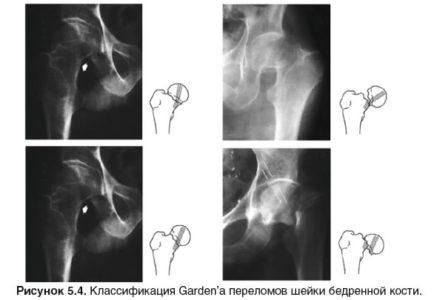

Виды переломов шейки бедра

Представляем вашему вниманию классификацию и меры профилактики перелома шейки бедра.

Типы переломов:

По анатомическому расположению:

- Трансцервикальный – проходит непосредственно через шейку бедренной кости.

- Базисцервикальный – располагается у основания шейки бедра.

- Субкапитальный – находится очень близко к головке бедренной кости.

Многие интересуются, насколько опасны трансцервикальный и базисцервикальный переломы шейки бедра. Второй тип, по сравнению с другими, имеет более благоприятный прогноз для сращивания костей и менее рискован, чем остальные.

Наиболее опасный тип перелома – субкапитальный, так как он значительно нарушает кровоснабжение головки. Ниже представлены изображения компрессионного и базального переломов.